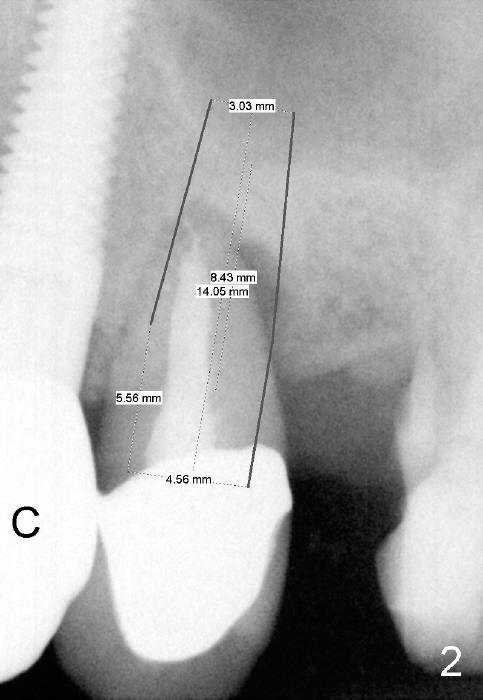

As soon as the tooth #12 is extracted and replaced with immediate implant, the patient feels that pain shifts to the tooth #13 (Fig.1 taken 3 months post implantation of #12; *: abutment). By the 7th months postop (Fig.2 C: crown), the patient agrees to have a 2nd implant for the tooth #13. Thorough debridement of the socket is planned. Sinus lift is expected. Take preop PA and photos.

To place bone graft efficiently, prepare 4 small pieces of gauze in a dap pen dish. Dissolve Clindamycin with 2% Xylocaine (or 4% Septocaine) with 1:50,000 Epinephrine. Use 3 pieces of gauze as usual, followed by normal saline irrigation. Thoroughly debride the socket, since there is a fistula buccodistally. Finish sinus lift and bone expansion/condensation with RT2,3, followed by 4.5x17 mm tap at the depth 14 mm. The first intraop PA is taken. If the bone is dense, use a 2 mm pilot drill to start osteotomy.

Use the last piece of the gauze for hemostasis before bone grafting. Wet the bone graft lightly with blood squeezed from the last gauze. Squeeze extra blood out of the bone graft inside the plastic dap pen dish with dry 2x2 and suction tip. Do it as quick as possible so that hemorrhage does not recur before bone grafting. Use 2.5 or 3.0 mm Bicon flat end osteotome to push bone graft into the sinus. A 4.5 or 5x14 mm tapered implant is to be used.